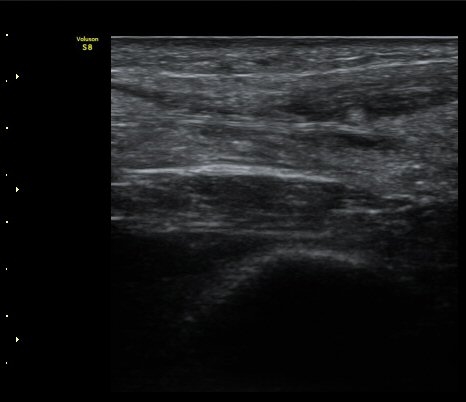

ÃÊÀ½ÆÄ °Ë»ç